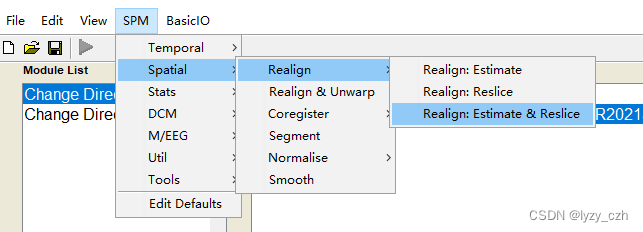

2) Realign,只需要编辑Session,其他参数不用改,编辑好后点击左上角绿色三角形按钮:

选择后要点一下要输入数据的地方不然可能会报错,如下图双击Data然后回多出一行Session这样就不会有问题了